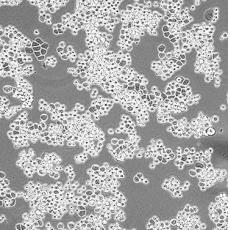

中文名稱 人乳腺癌細胞

組織來源 乳腺腺癌;胸腔積液轉移;女性

生長特性 adherent

形態特征 epithelial

細胞描述 該細胞系由CailleauR在1976年從一名48歲的患有轉移性乳腺癌的白人女性的心包滲出液中分離建立的。該細胞表達FGF的受體。